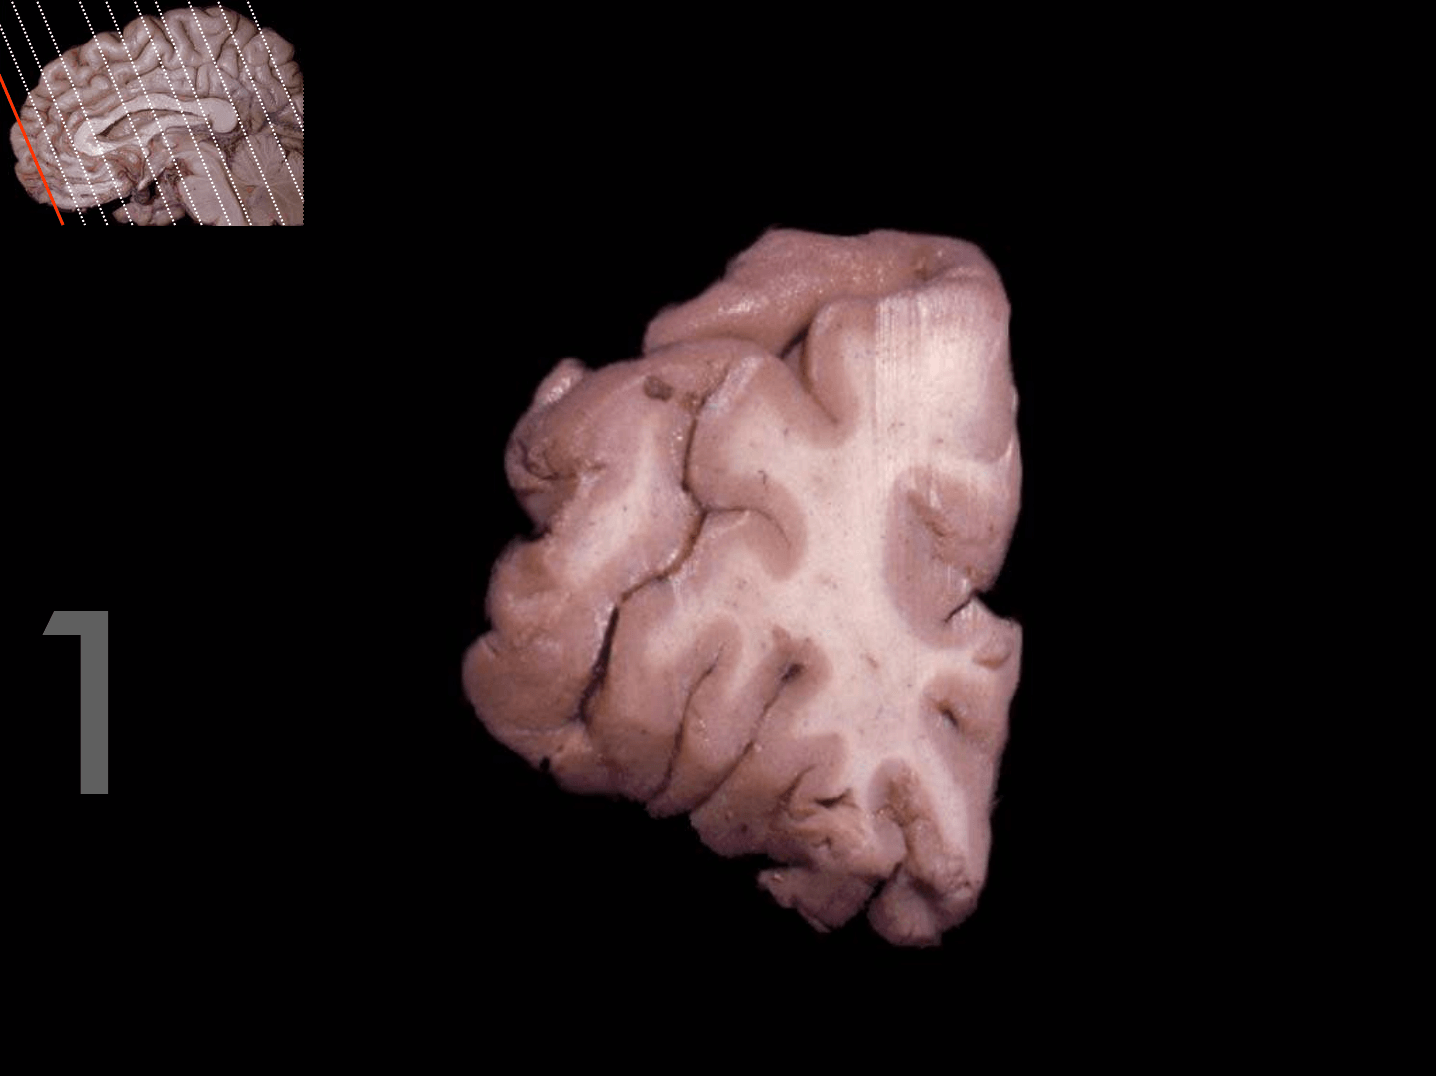

Tronco del cuerpo calloso

Rodilla del cuerpo calloso

Columna del fórnix

Comisura anterior

Foramen interventricular

Infundíbulo

Habénula

Pico del cuerpo calloso

Acueducto del mesencéfalo

Estría medular del tálamo

Adhesión intertalámica

Lámina terminal

Quiasma óptico

Tubérculo mamilar

Comisura posterior

Glándula pineal

Rodete del cuerpo calloso

Calota mesencefálica

Túber cinereum